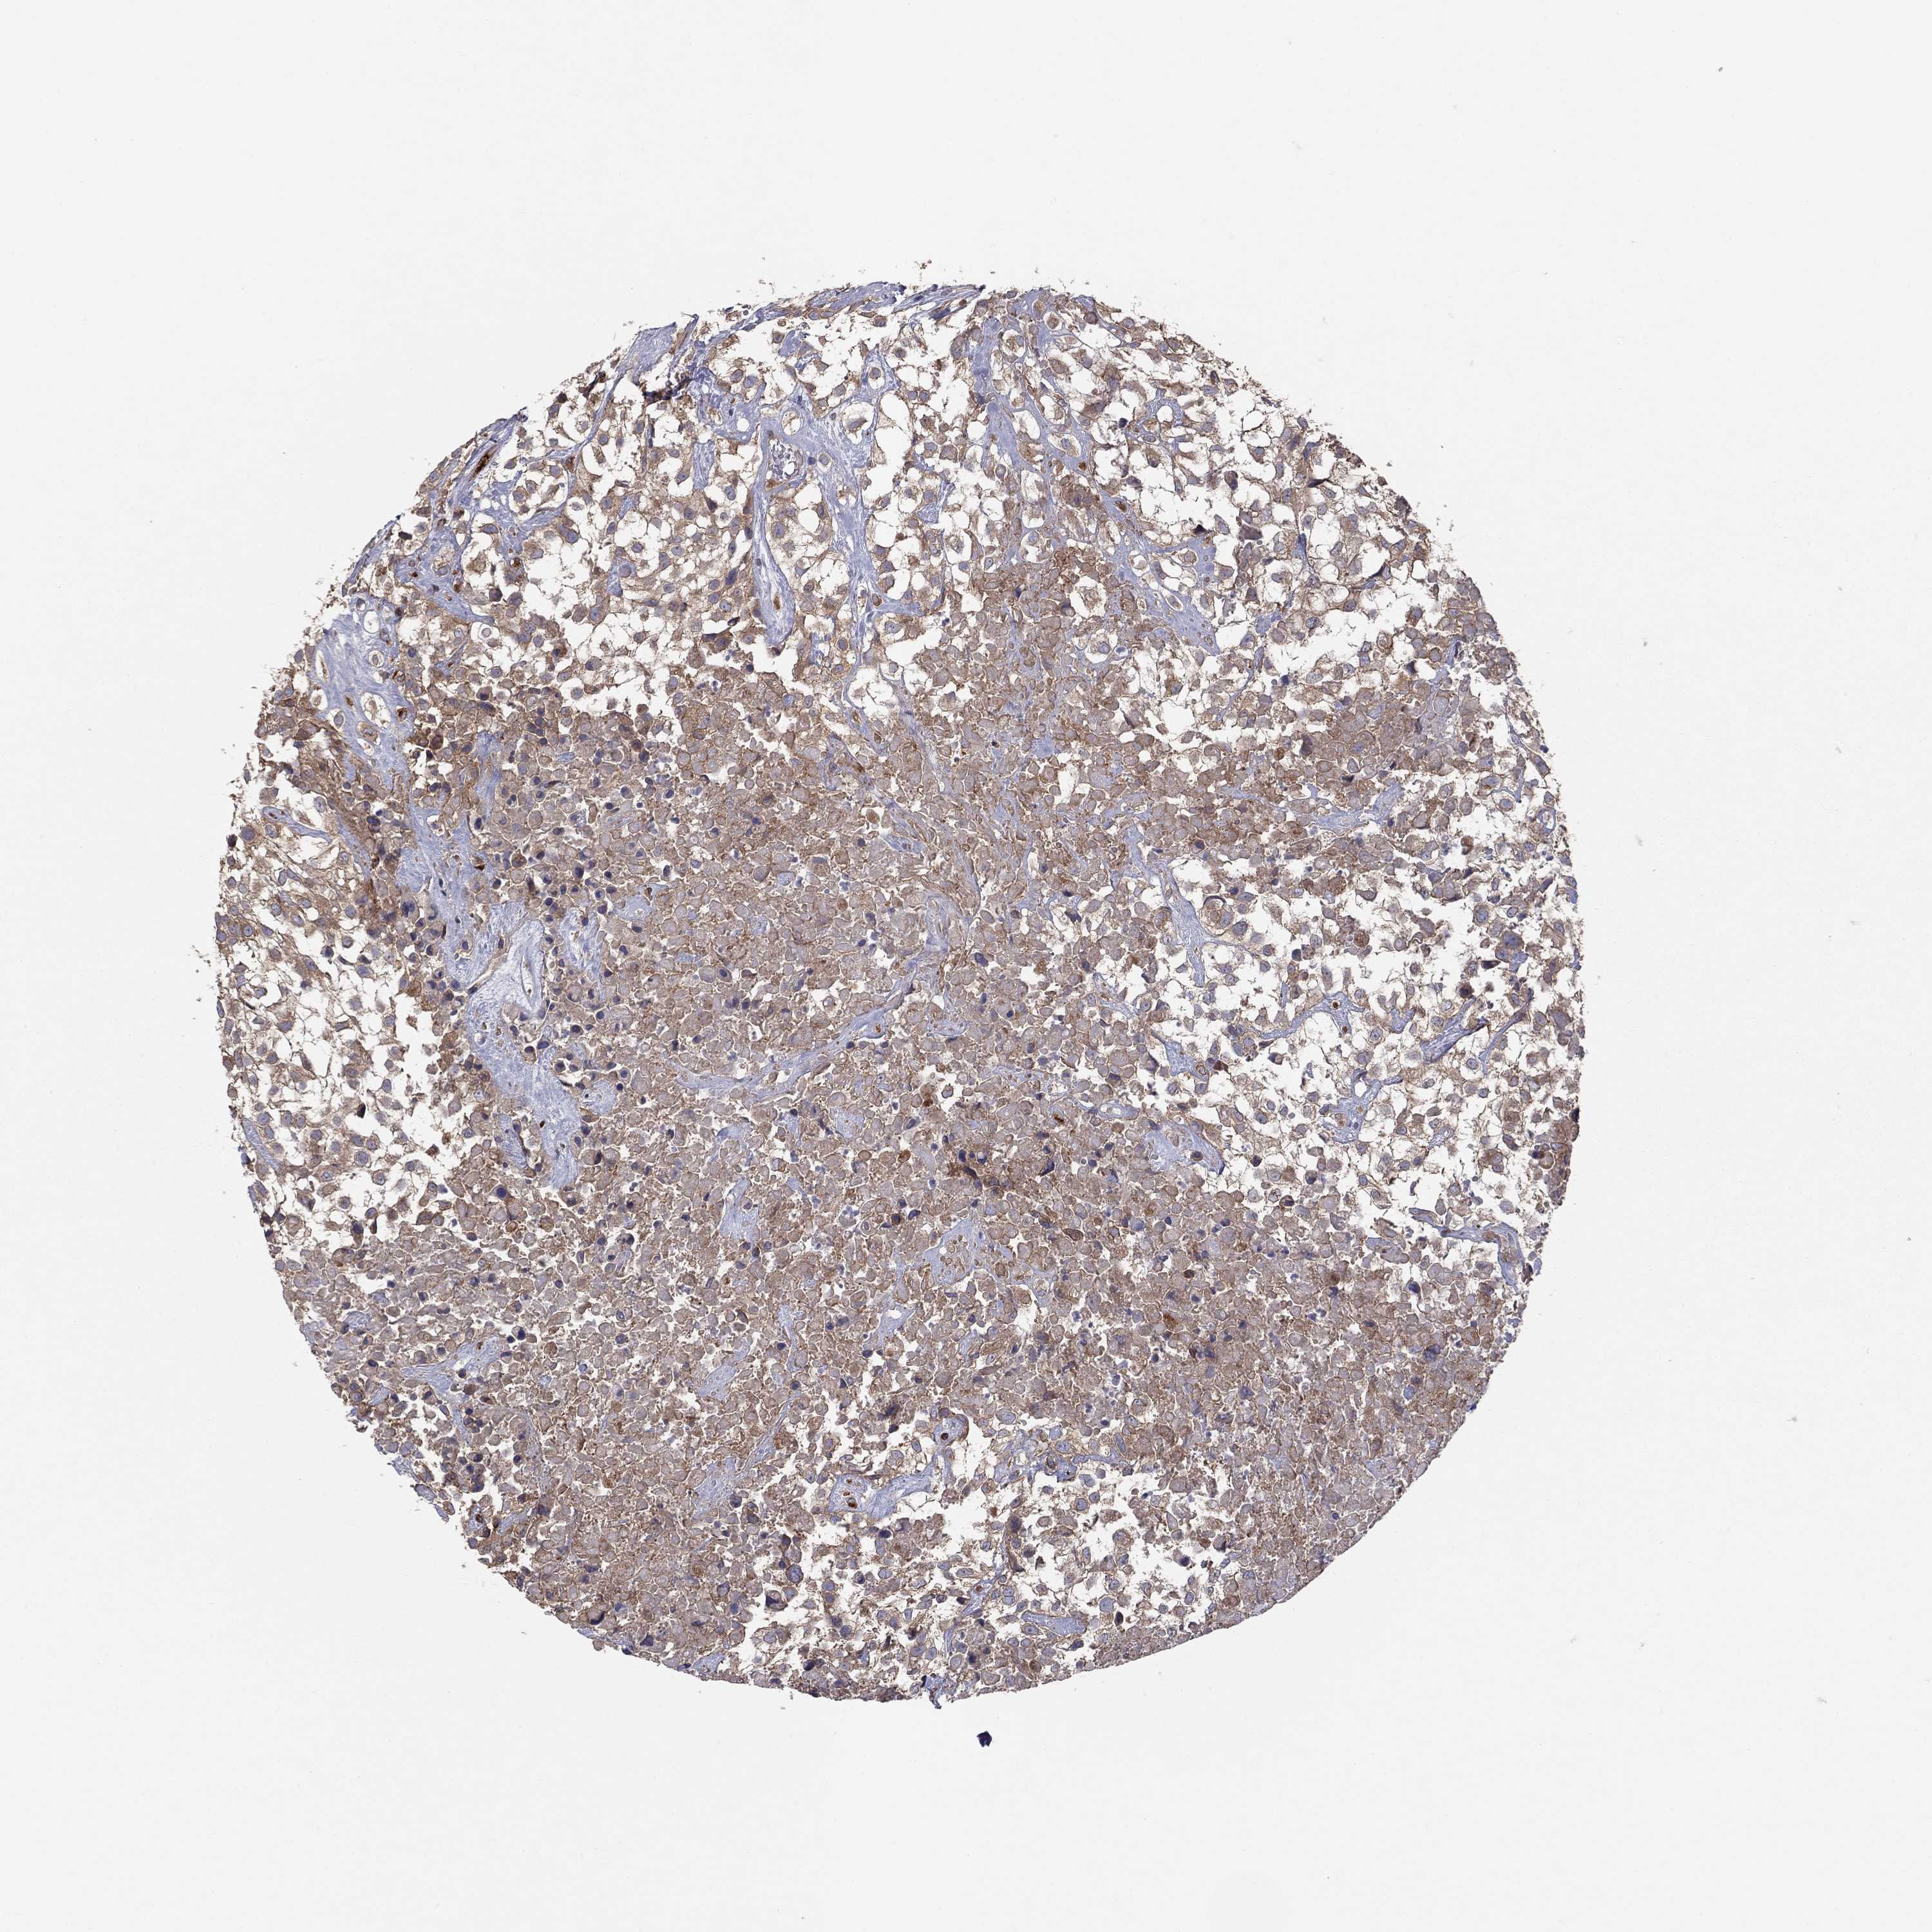

UROTHELIAL CANCER - Protein expressioni

A mouse-over function shows sample information and annotation data. Click on an image to view it in a full screen mode. Samples can be filtered based on level of antibody staining by selecting one or several of the following categories: high, medium, low and not detected. The assay and annotation is described here.

Note that samples used for immunohistochemistry by the Human Protein Atlas do not correspond to samples in the TCGA dataset.

Antibody stainingi

Antibody staining in the annotated cell types in the current human tissue is reported as not detected, low, medium, or high, based on conventional immunohistochemistry profiling in selected tissues. This score is based on the combination of the staining intensity and fraction of stained cells.

Each image is clickable and will lead to virtual microscopy that enables deeper exploration of all samples and also displays staining intensity scores, fraction scores and subcellular localization as well as patient and tissue information for each sample.

Antibody HPA076194

Staining

High

Medium

Low

Not detected

Intensity

Strong

Moderate

Weak

Negative

Quantity

>75%

75%-25%

<25%

None

Location

Nuclear

Cytoplasmic/membranous

Cytoplasmic/membranous,nuclear

Urothelial carcinoma, High grade

Urothelial carcinoma, Low grade